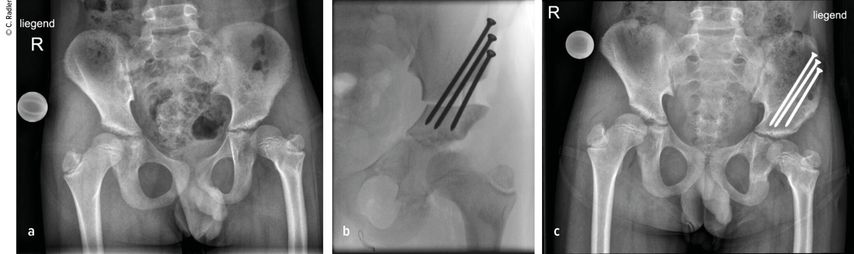

Milde Formen – Typ 1A – zeigen oft nur einen leichten Schenkelhalsvarus und eine verminderte femorale Antetorsion beziehungsweise Retroversion zusätzlich zur Verkürzung. Oft zeigt sich bei diesem Typ auch eine milde subtrochantäre Varusstellung und Sklerose. Mit zunehmendem Schweregrad addiert sich eine azetabuläre Dysplasie, wobei besonders die obere und hintere Überdachung der Hüfte vermindert ist. Beim Typ 1A ist in seltenen Fällen keine vorbereitende Operation erforderlich, insbesondere wenn die Überdachung der Hüfte sehr gut ist und ein CE-Winkel von über 20 Grad vorliegt. Es kann dann direkt mit einer Verlängerung des Femurs begonnen werden. Je nach verwendeter OP-Technik können eine eventuell vorhandene Retroversion und Varusstellung im Rahmen der Verlängerungsoperation akut über eine zusätzliche proximale Osteotomie und Montage an den oberen Teil des Fixateurs adressiert werden. (Abb.1).

Abb. 1: Operative Versorgung eines CFD rechts mit Varusstellung an der Hüfte und subtrochantärer Sklerosierung

In allen Fällen, in denen eine – wenn auch nur grenzwertige – Dysplasie des Acetabulums vorliegt, ist vor einer Verlängerung eine Beckenosteotomie (Acetabuloplastik) erforderlich.

Im Rahmen dieser Operation können auch die Retrotorsion und der Schenkelhalsvarus korrigiert werden. Eine Verlängerung bei nicht optimal überdachter Hüfte führt meist zu einer Subluxation oder Luxation, was eine schwerwiegende Komplikation darstellt, die nur schwer und meist nicht folgenlos zu beheben ist. Auch bei älteren Patienten ist die Überdachung vor einer eventuellen Verlängerung zu überprüfen, wobei besonders ab dem 4. Lebensjahr eine Tripelosteotomie eine bessere Überdachung und Einstellung der Pfanne gegenüber einer Acetabuloplastik erlaubt (Abb.2).

Abb. 2:Versorgung eines kurzen Pfannendachs mittels Tripelosteotomie, um die Hüfte während der Verlängerung vor (Sub-)Luxation zu schützen